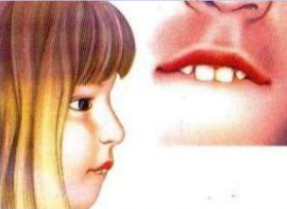

Característiques facials

Les característiques facials poden ser:

Cara estreta i llarga

Altura facial inferior augmentada

Malposició dentaria amb incisius a la vista

Bosses palpebrals (bosses de greix sota els ulls)

Galtes flàccides

Nas petit i respingona

Orificis nasals petits i pocs desenvolupats.

Curtesa dels llavis i posició entreoberta de la boca.

Llavi superior curt i incompetent.

Llavi inferior gruix i caigut.

Borla de la barbeta hipertònica.

Perfil convex moderat o sever.

Protrusió del maxil·lar superior